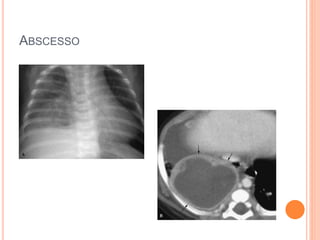

CAVIDADES: ABSCESSOS

 Complicação de PNM bacteriana

 Parede espessa e irregular, nível HA

 TC: útil para diferenciar abscesso X empiema loculado

no espaço pleural

ABSCESSO